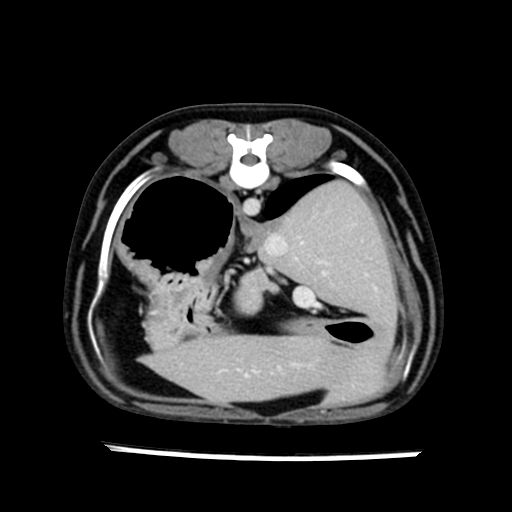

prescritto esame TAC

sequenza immagini limitata al fegato reni e surreni

le immagini ecografiche rispetto alla tac datano circa 7 mesi prima ,le surrenali sono normali nonostante il test acth sia risultato positivo .all’esame TAC dopo diversi mesi risultano aumentate armonicamente nel volume e si individua un forte sospetto di adenoma ipofisario .

sospetto adenoma ipofisario vs. meno probabilmente meningioma della base; intertiziopatia polmonare; lesione espansiva epatica, verosimilmente del lobo laterale sinistro, di sospetta natura neoplastica; lesioni spleniche di natura da definire; iperplasia/ipertrofia delle ghiandole surrenali, bilateralmente; vertebra di transizione del rachide toracico; tenosinovite cronica del muscolo bicipite brachiale di destra.

- l’esame tac e’ stato eseguito circa quattro mesi dopo la prima ecografia che non aveva messo in evidenza aumento del volume surrenalico (vedi immagini) ma solo la lesione epatica, la presenza di PU PD aveva portato ad un controllo per l’ ipercorticosurrenalismo confermato dal test act , in questo caso, si deduce che i sintomi di ipercorticosurrenalismo legati all’adenoma sono comparsi prima delle modificazioni surrenaliche, quindi in caso di sospetto ,a mio avviso e’ buona norma eseguire prima il test di stimolazione e dopo L’ECOGRAFIA per tentare una classificazione eziopatogenetica . La Tac si e’ quindi dimostrata molto valida in sensibilita’ e specificita’ riguardo la patologia surrenalica in quanto in grado di vedere o fortemente sospettare (ovviamente meno sensibile della RM) un piccolo adenoma ipofisario e le alterazioni morfovolumetriche della surrenale.

- la total body permette di escludere metastasi e di avvicinarsi all’interventistica